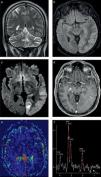

En los últimos años, se ha destacado la importancia de utilizar esta secuencia con pulsos de saturación grasa y luego de administrar el medio de contraste: mientras la primera aumenta el contraste entre la sustancia gris y blanca, con una mejora consiguiente de la resolución; la poscontraste tiene una mayor sensibilidad en la detección de alteraciones meníngeas, tanto de colecciones líquidas (sobre todo empiemas subdurales) como del compromiso leptomeníngeo observado en las meningitis de distinta etiología8–10 (fig. 1).

Paciente con meningitis tuberculosa confirmada. Se muestra la utilidad y los hallazgos de la secuencia FLAIR luego de administrar el contraste. (a, b y c) En los cortes axiales se identifica el intenso realce y la ocupación de la cisterna de Silvio del lado derecho por el depósito de material granulomatoso (característico de esta patología). (d, e y f) Mismo paciente: en los cortes sagital y axial de la secuencia SE ponderada en T1 con contraste se observan los hallazgos ya identificados claramente en la secuencia anterior.

Algunos autores sugieren que la sensibilidad de las secuencias FLAIR posgadolinio y las ponderadas en T1 es idéntica en el diagnóstico de la patología infecciosa leptomeníngea, pero que la FLAIR tiene mayor especificidad10. Incluso, otras comunicaciones, como la de Splendiani et al.11, demuestran la utilidad de la RM con secuencias FLAIR poscontraste en el diagnóstico precoz de casos con meningitis infecciosa. No obstante, a pesar de estos estudios y de que nuestra experiencia sea muy similar en un número significativo de pacientes, es necesario destacar que las secuencias convencionales ponderadas en T1 con contraste no son sustituibles en esta población.